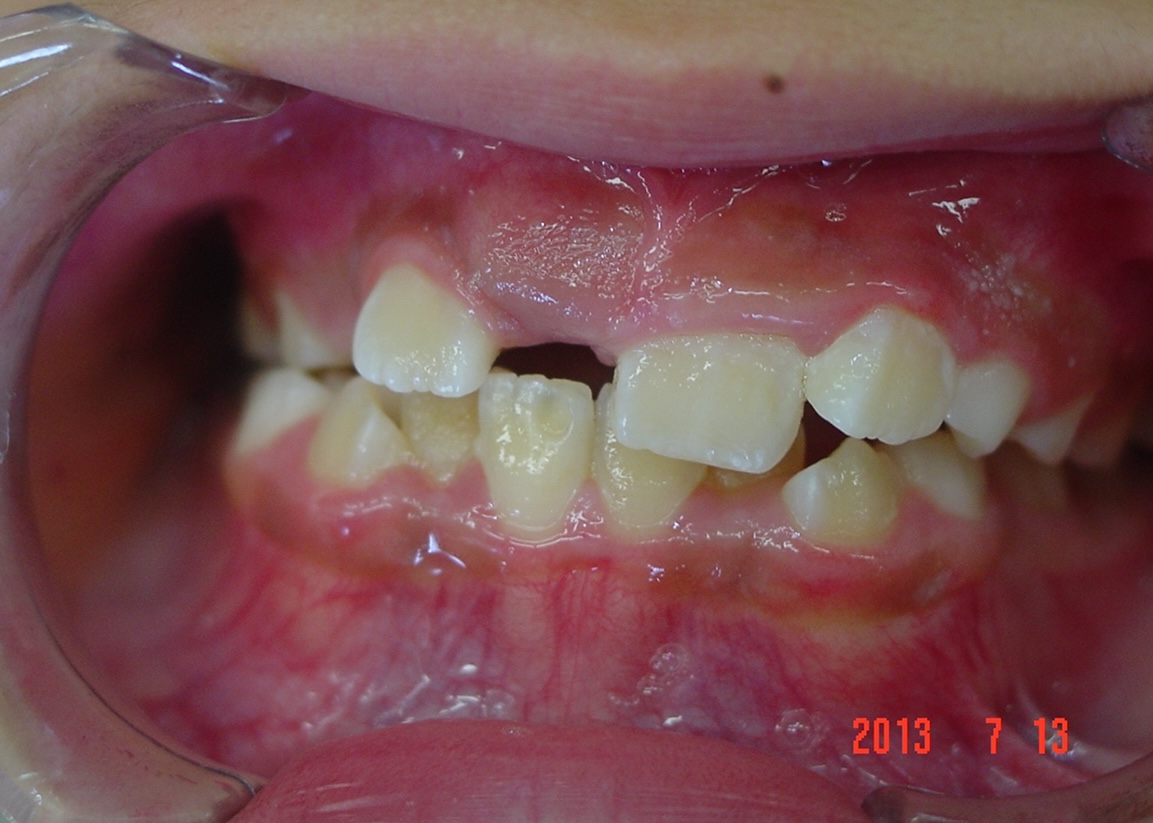

矯正前

| 症状 | 左上2番3番逆転症例 |